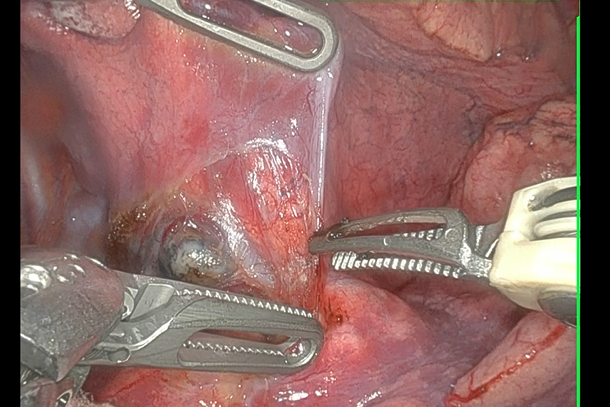

当院では、2022年から手術支援ロボット(ダヴィンチ)による肺がん手術を行っております。

手術は、図の如く3-4cmの皮膚切開1箇所と1-2cmの皮膚切開4箇所で行います。

医師はカメラで映し出された画像を見ながら、ロボットアームを操作して手術を行います。ロボットアームは医師の手と連動していて、狭い空間でも自分の手の如くに操作ができます。

医師が見るカメラの画像は、デジタルズーム機能で10倍まで拡大して見ることができます。また、操作する医師の手先の震えがロボットアームに伝わらないように、手ぶれを補正する機能もあり、緻密で正確な手術が可能になります。

| ▲肺がん手術の様子 |